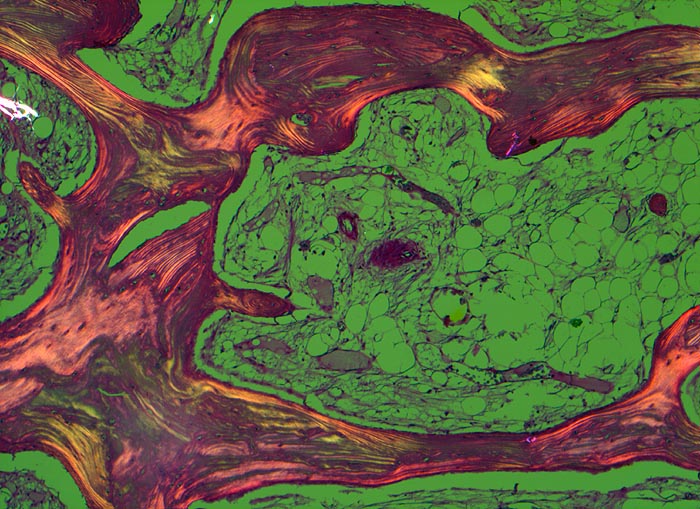

Makroskopisch ist die Nekrose im Anfangsstadium durch eine intensiv gelbe Verfärbung mit hämorrhagischem Randsaum charakterisiert. Häufig kommt es zur flächenhaften Ablösung des ansonsten intakten Gelenkknorpels (DD Arthrose!) zwischen subchondraler Knochenlamelle und angrenzender Spongiosa. In den Spätstadien sind die Nekrosezonen grau-gelb gefärbt und von körniger Konsistenz. Ein Teil der nekrotischen Spongiosabälkchen dient als Leitschiene für die Neubildung von Osteoid und mineralisierten Trabekeln, die an der Aussenseite angelagert werden. In der Nekrosezone kommt es zur Sequestrierung von Knochenbälkchen durch Frakturen. Die Markräume werden bindegewebig organisiert. In der Peripherie besteht initial ein hyperämischer Randsaum und im Verlauf kommt es zur Ausbildung einer metaplastischen Knorpel- und Knochenneubildung mit Randsklerose. Das Endstadium der Abräumreaktion untergegangener Knochenabschnitte stellt eine meist subchondral lokalisierte pseudozystische Umwandlung dar. Schliesslich kollabiert der Femurkopf und der Verlust der Gelenkkongruenz führt zu einer fortschreitenden sekundären Coxarthrose (> 3192)

• Flächenhafte Ablösung des gut erhaltenen Gelenkknorpels zwischen subchondraler Knochenlamelle und angrenzender nekrotischer Spongiosa.

• In der Nekrosezone osteoklastäre Resorption von avitalen sequestrierten Spongiosabälkchen.

• Ortsständiger Lamellenknochen wird als Leitschiene zur Fasernknochenneubildung benutzt.

• Pseudozystische Hohlräume in den nekrotischen Markräumen.

• Fibrosiertes Mark mit einzelnen thrombosierten Arterien.